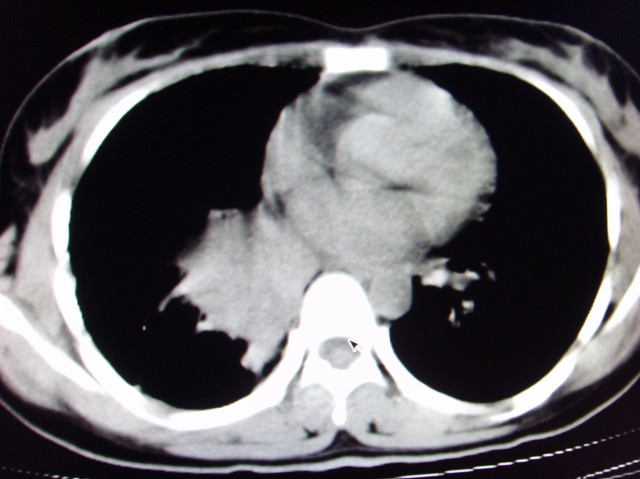

标题: CT7125:中央性肺Ca.

典型 中央型ca伴双肺、淋巴结转移

典型的中央型ca,肿快和肺门分界不清,肿快边界模糊,呈毛刺状。伴淋巴结转移。